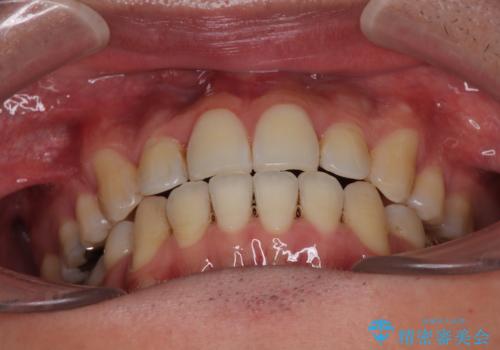

抜歯したスペースを活用して前歯を後ろへ下げることで、口元の突出感を大きく改善。

奥歯の噛み合わせがずれている「シザーズバイト」を適正に整えることで、見た目だけでなく機能性も向上し、安定した咬合が獲得できました。

口元の突出が改善され、横顔の印象が大きく変化し、口が自然に閉じやすくなりました

前歯のデコボコが整い、清掃性が向上

噛み合わせが改善し、長期的に安定する噛み合わせに

「見た目」と「機能性」の両方を改善できた、非常に満足度の高い治療となりました。